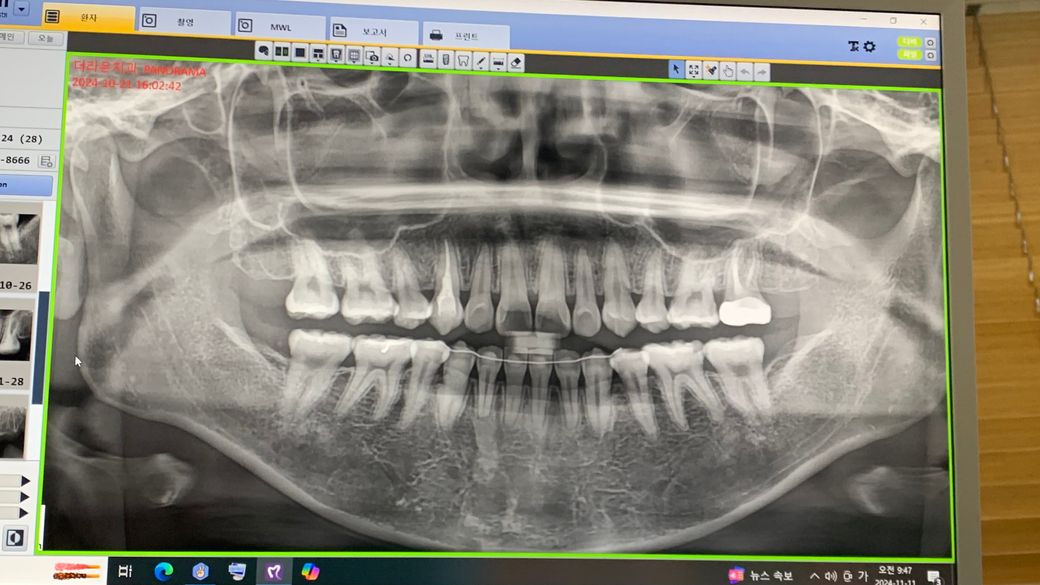

파노라마 ㅇ) 신경치료를 할만한 치아인지 한번 봐주세요!ㅠ

26번치아가 썩었다고 해서 신경치료를 받았습니다..

충치가 있는건 맞는 것 같은데

아무리생각해봐도 이게 신경치료를 할만한 치아인지 모르겠어요. 과잉진료 같아서요

충치가 많이 깊어 보입니다. 26번 치아 뒤쪽으로 충치가 있어서 신경치료 가능성이 사진상으로도 있어 보입니다.

신경치료 까지 들어갈 지 여부는 확실하지 않지만 가능성은 충분히 있으며 치근단 사진이 더 도움이 됩니다.

신경치료를 하게 되는 경우는 치아에 금이 간 경우, 심하게 깨지거나 마모된 경우, 충치가 깊은 경우입니다. 위 엑스레이 사진상에서는 아주 깊은 충치는 보이진 않습니다만 진단에 대해서는 이렇게 온라인 상에서 보는 것보다 직접 치아를 보고 여러 임상검사를 한 치과가 훨씬 정확할 것입니다.